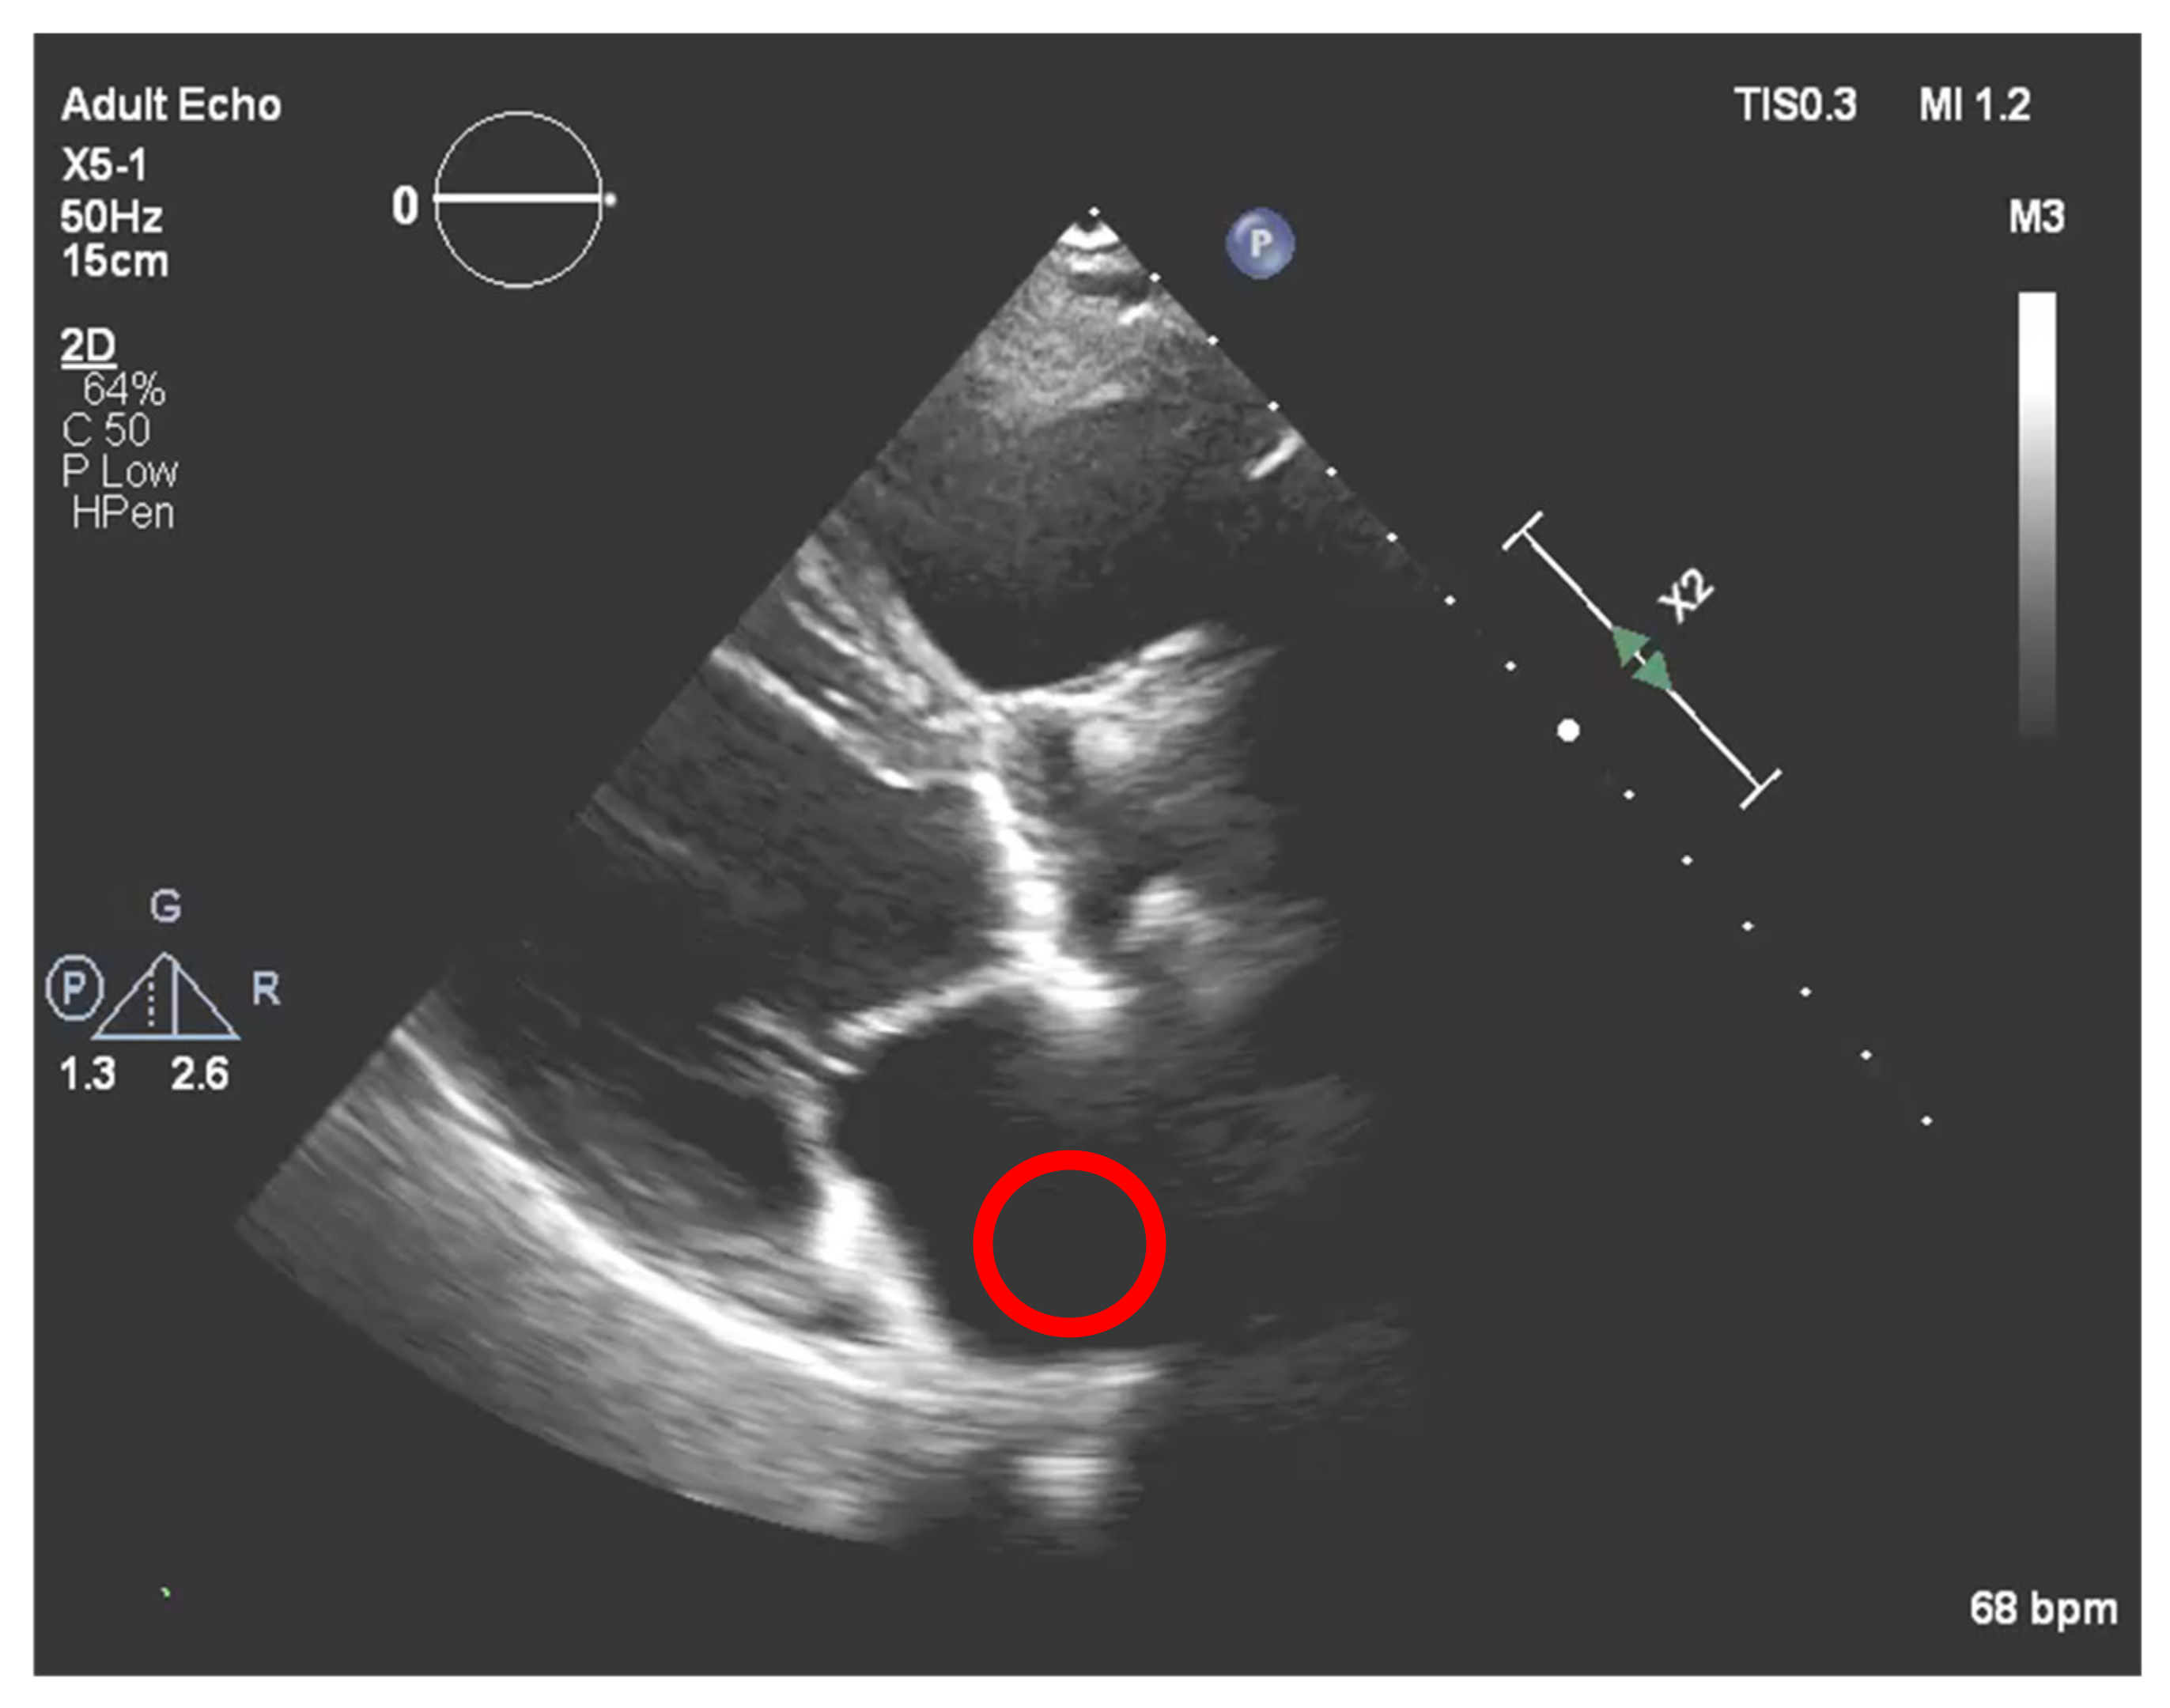

Nevertheless, this simple approach relying solely on histogram equalization leads to poor and inconclusive results in terms of visualizing and extracting the presence of calcium, as shown in Figure 1. The red circle represents where there is calcium on the aortic valve, and in yellow, other structures are marked, which are indistinguishable from each other.

Figure 1. Echocardiography image with CLAHE—The red circle represents the region of interest (ROI) where the calcified aortic valve is located, and in yellow, other structures are marked, which are non-calcified structures.